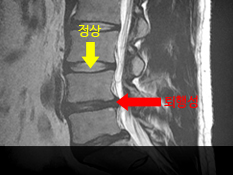

̰ ôߵ Բ ľϴ. ǰ ôߴ 30 ̾ ִµ, ױ̰ ձϰ ̿ ִ ũ ¸ ϰ ֽϴ. ô߰ ũ ũ 鼭 ϴ. ̿ ء̶ ð ڶϴ. ̷ ༺ ũ ũ ڴ ڶ ֺ Ű ڱ Ÿϴ. Ϲδ 50~60뿡 ̴ μ ȯ̸ ַ ٴ , ֱٿ 30~40 ϴ 찡 ϰ ֽϴ. ༺ũ Ӹ ƴ϶ ߿ ϴ ôȯԴϴ.